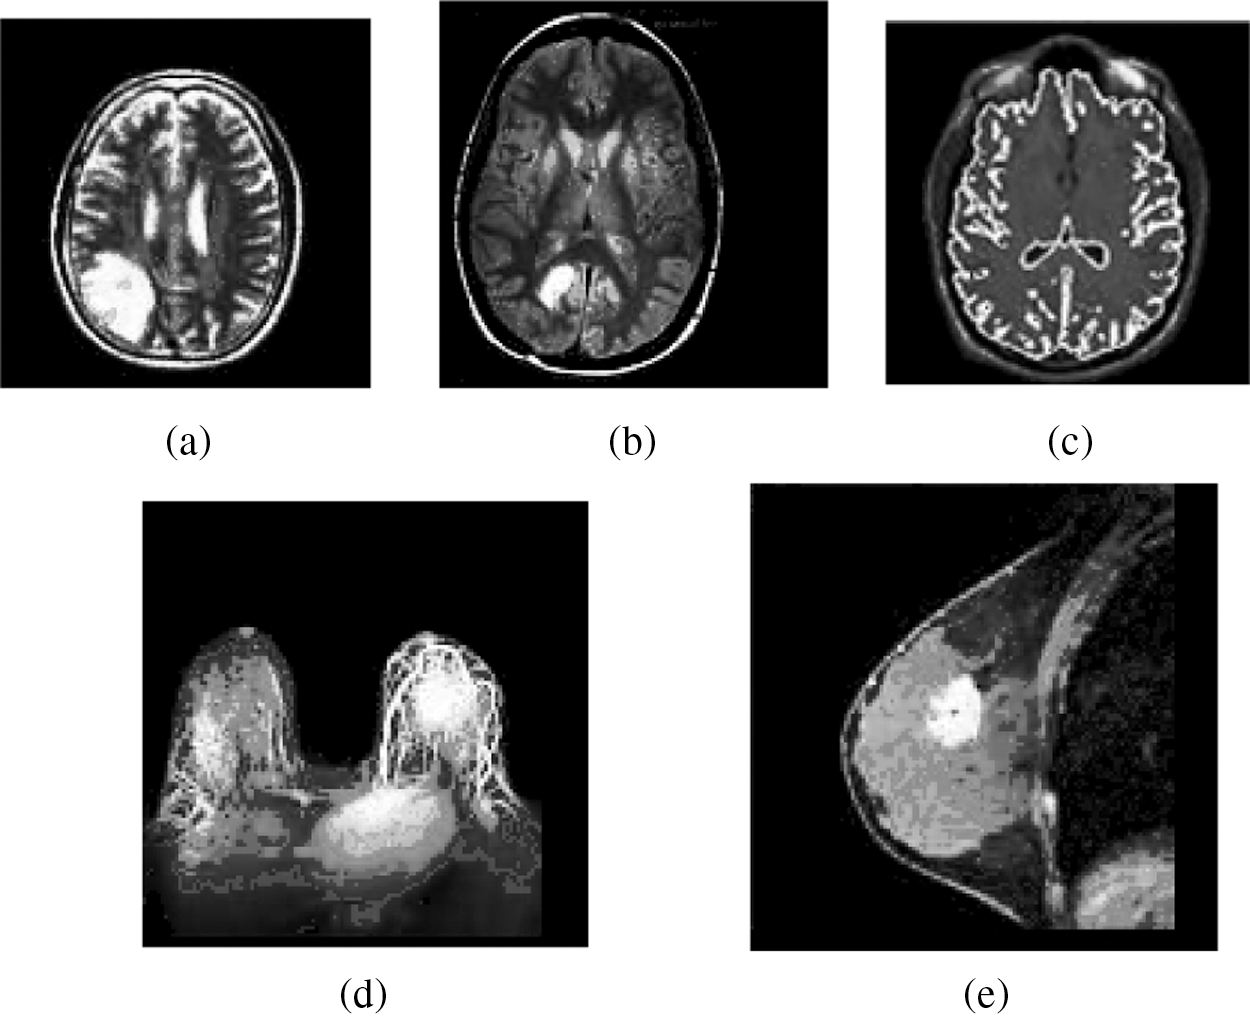

Figure 3: Result of the MIPC scheme tested on the ten gray scale MR images using DAAC approach indicated in Fig. 2: (a) Result of brain_1 (b) Result of brain_2 (c) Result of brain_3 (d) Result of breast_1 (e) Result of breast_2

Similarly, the MIPC approach detects distinct number of unrelated clusters on same five MR image datasets based on DAAC scheme. Primarily, it automatically traces the distinct representative objects over the five MR images as illustrated in Fig. 2 based on frequency of maximum occurrence (MO = 15) and the count of distinct representative objects are obtained in Tab. 2 as 33, 27, 33, 39, 27 respectively. The Maximum Occurrence is a predetermined threshold which used to dynamically find the appropriate number of distinct representative objects in dataset. Then it followed by sequence of merging process and divides the each individual image dataset into distinct number of dissimilar clusters based on count of representative objects as presented in Tab. 3. In the case of sample gray scale image datasets presented in Fig. 3, the clustering scheme could identify 33, 27, 33, 39 and 27 distinct clusters. The resulting clusters of the clustering scheme are incorporated in the Tab. 2. Fig. 3 demonstrates the clustering result of the MIPC (DAAC) on five gray scale MR images Brain_1, Brain_2, Brain_3, Breast_1 and Breast_2 as obtained in Figs. 3a–3e, 3 respectively.